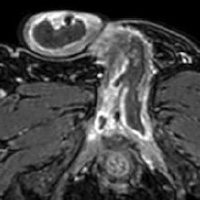

Renal myxoma: An unforeseen diagnosis